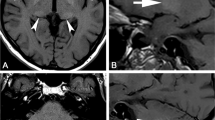

Experimental SNR and parametric estimates

Figure 3 shows the typical SNRb1000 obtained with our experimental setting. SNRb1000 is higher in the cortical gray matter than in the deep gray matter partly as a consequence of coil sensitivity. For white matter, SNRb1000 is also dependent on the fibre orientation with respect to diffusion encoding. In Fig. 3b, the SNRb1000 histogram is obtained based on the masks in Fig. 3a. The average SNRb1000 is ~8 for a single measurement, and can be related to the SNR when multiple repetitions are averaged. For example, the SNR averaged over 12 repetitions is 8 times the square root of 12, which is ~30 (one of the values we chose to demonstrate in Fig. 1).